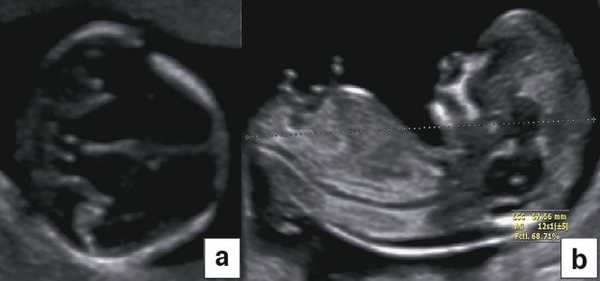

Диагноз хориальности и количества амнионов

УЗИ при двойне в основном должно выявить хориальность (ди- или монохориальность) и для монохориальных беременностей (моно- или диамниотических) - количество амнионов. При многоплодной беременности эта информация необходима для соответствующего ведения дискордантной мальформации, замедления роста, внутриутробной гибели плода или получения образцов ткани плода. Точность этой диагностики в течение I триместра может достигать 100%, а затем на протяжении беременности она уменьшается [7]. Дихориальность подтверждают выявлением лямбда-признака (рис. 4a). Наоборот, монохориальность диагностируют при отсутствии визуализации лямбда-признака или выявлении T-признака (рис. 4b) в межамниотической мембране, расположенной перпендикулярно хорионической пластине.

Рис. 4. Диагностика хориальности и количества амнионов в I триместре путем оценки лямбда-признака (a) и T-признака (b).